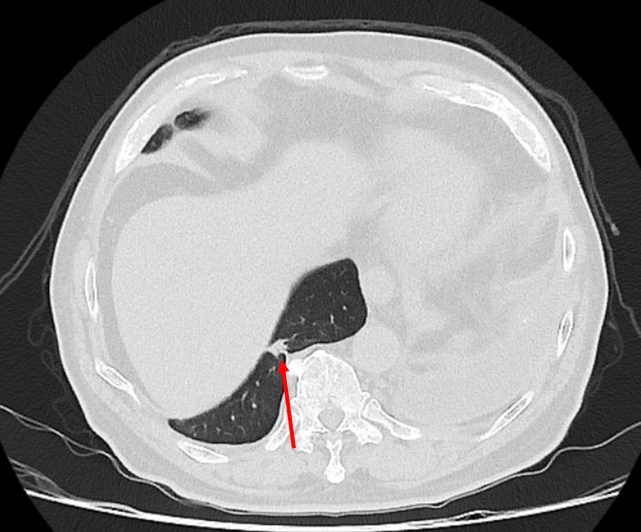

▲電腦斷層顯示病人的肺結節位於橫膈膜正後方。(圖╱仁愛長庚醫院提供)

廖啟耀主任表示,雖然肺臟腫瘤手術在台灣十分普及且發達,但是有些病人的情況會使醫師預期手術難度提高,其中以過去有過外傷經歷、曾經接受過胸腔手術、肺臟腫瘤接受過放射性治療的病人最為常見,這類病人常見的手術困難度為解剖構造的改變,常因為胸腔發炎反應的影響,讓肺臟與周遭肋膜產生沾黏,同時血管的方向也更難分辨,對執行手術醫師而言是一項困難的挑戰。